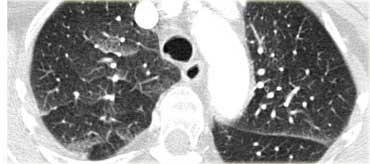

Sarcoidosis: hình ảnh điển hình với các nốt dọc theo bó mạch phế quản và các khe liên thùy. Lưu ý hạch vôi hóa một phần ở rốn phổi trái.

Hình ảnh điển hình của sarcoidosis với hạch to rốn phổi và các nốt nhỏ dọc theo bó mạch phế quản (mũi tên vàng) và dọc theo các khe liên thùy (mũi tên đỏ).

Hình ảnh chi tiết với biểu hiện HRCT điển hình gồm các nốt dọc theo bó mạch phế quản (mũi tên đỏ) và các khe liên thùy (mũi tên vàng).

Đây là phân bố theo đường bạch huyết điển hình của các nốt.

Bên trái là một hình ảnh điển hình khác của sarcoidosis với hạch to trung thất và các nốt nhỏ phân bố theo đường bạch huyết dọc theo bó mạch phế quản và dọc theo các khe liên thùy (mũi tên vàng).

Luôn tìm kiếm các nốt nhỏ dọc theo các khe liên thùy, vì đây là dấu hiệu rất đặc hiệu và điển hình của sarcoidosis.